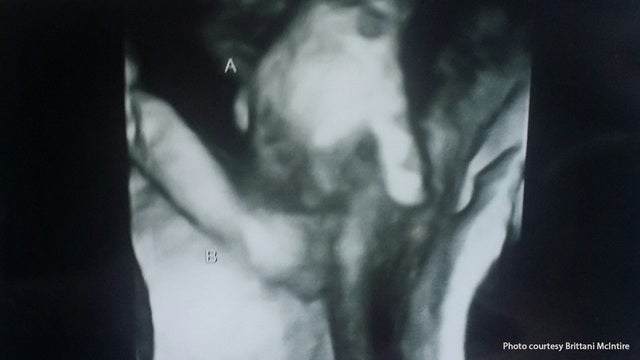

Touching sonogram image shows dying twin holding sister's hand

A Kansas family has a touching moment during a very difficult time. A sonogram this week shows a twin, who is not expected to survive, holding the hand of his sister in the womb.